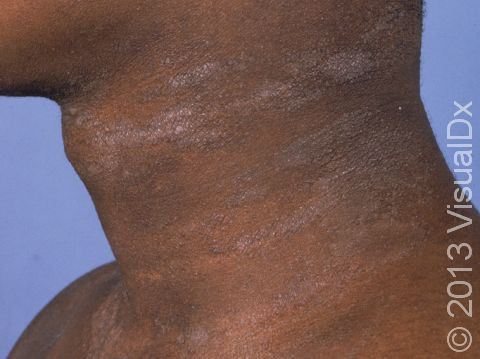

Although lichen simplex chronicus can occur anywhere on the body, it is most commonly seen in the following areas:

- Inner wrists, forearms, and elbows

- Sides and back of the neck

Each patch of lichen simplex chronicus appears as leathery, thickened skin in which the normal skin lines are exaggerated. The thickened skin is darker than surrounding skin (hyperpigmented). This hyperpigmentation is even more apparent in darker-skinned individuals.